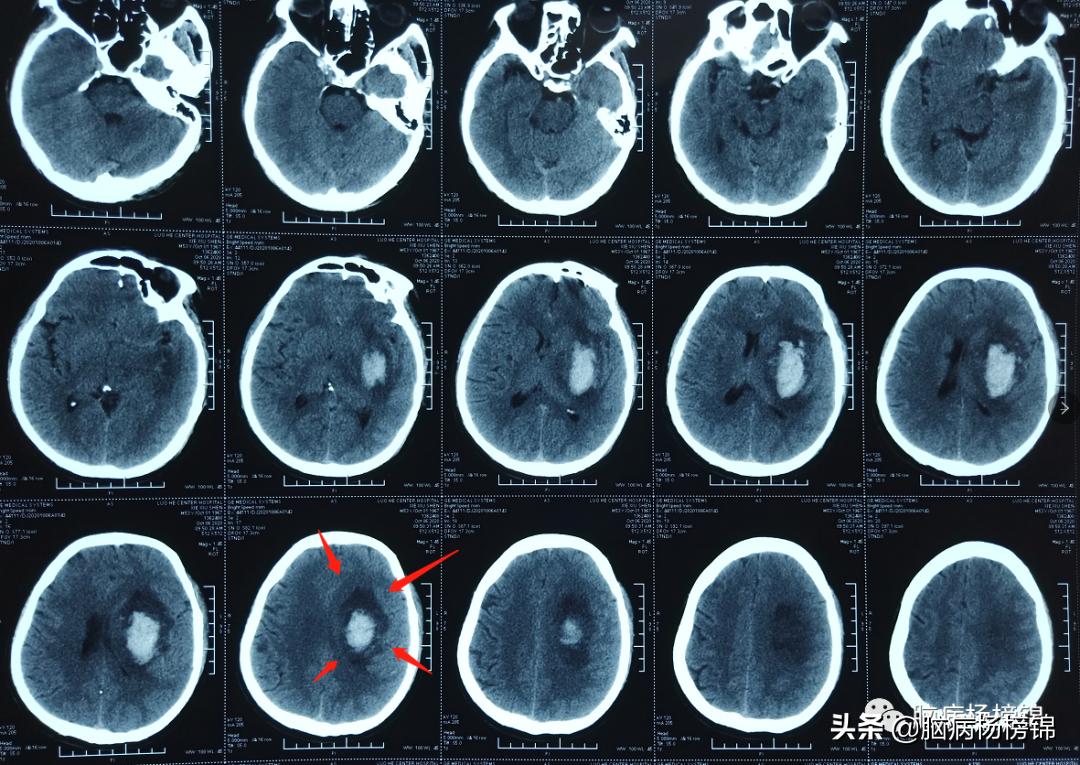

漯河市第一人民医院急诊颅脑CT,脑出血。

保守治疗六天,病情稳定。

保守治疗16天,血肿开始吸收。